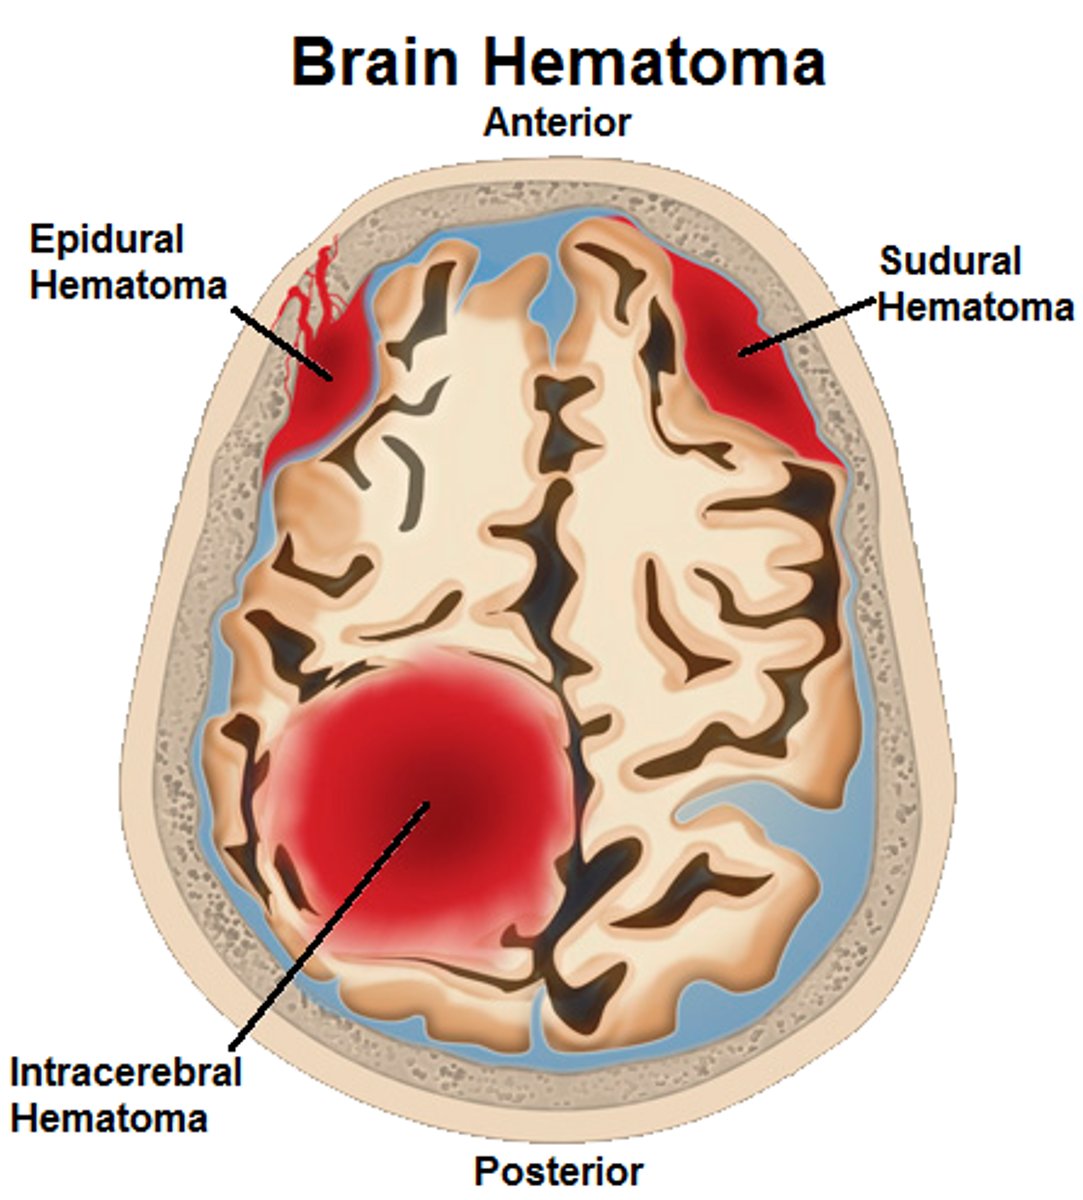

Types of Head Trauma

Concussion,

Contusion,

Subdural Hematoma,

Cerebral Edema

Concussion

Alteration in brain function following blow to the head

Contusion

Bruising in the brain and can cause permanent Neurological Damage

Subdural Hematoma

Blood vessels are broken in the brain

Cerebral Edema

Swelling on the brain